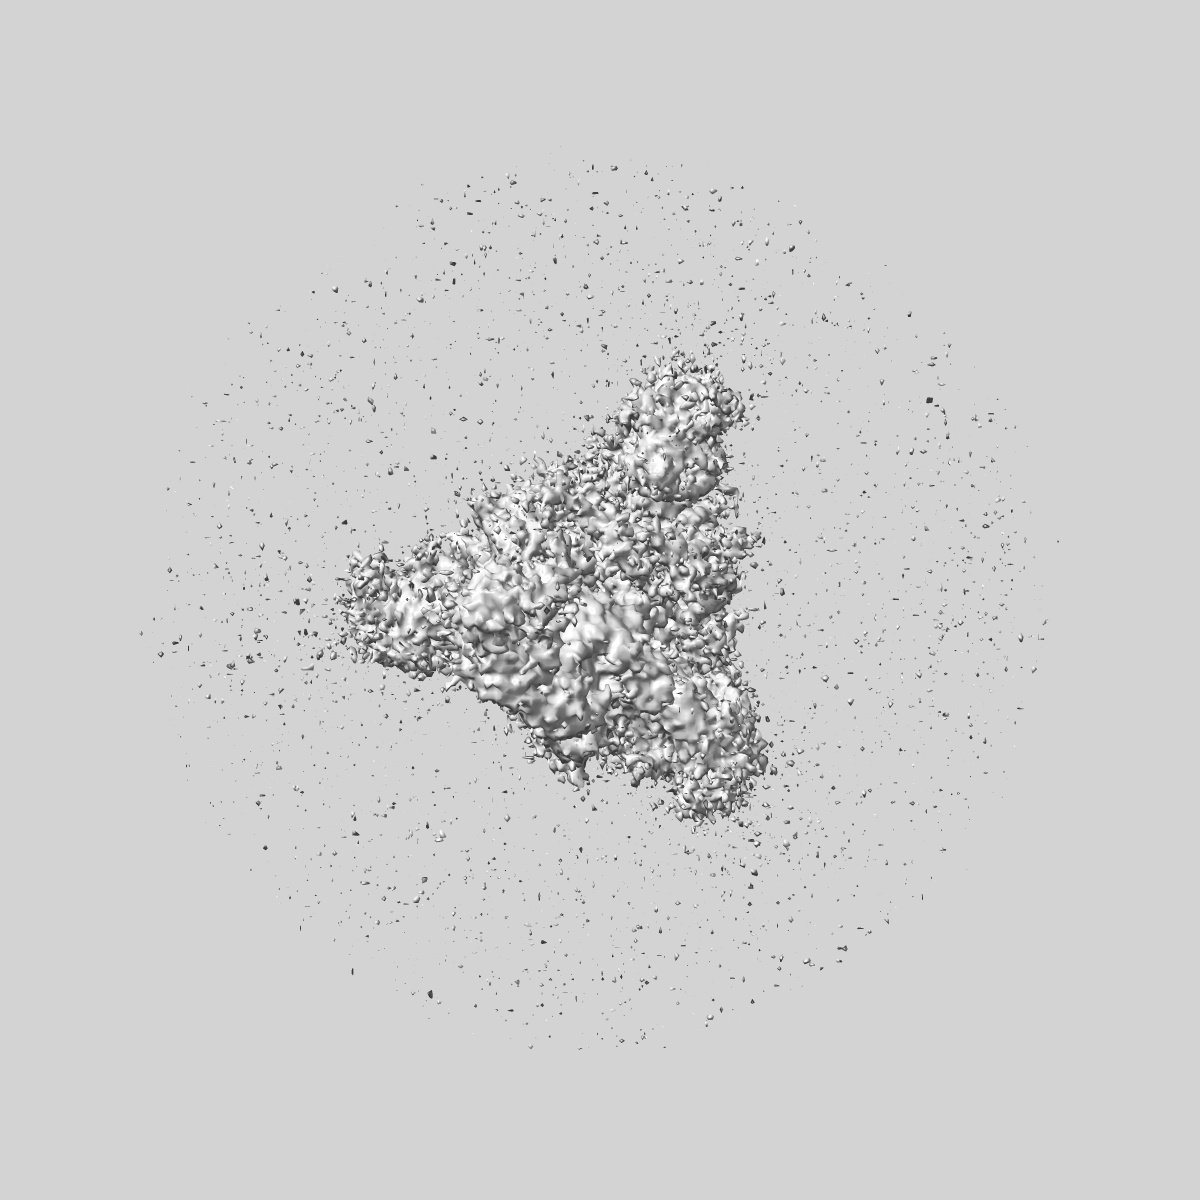

SARS-CoV-2 Wuhan Spike ectodomain in complex with human polyclonal antibody ModWu-RBD2 (mRNA-1273 vaccine)

Sample: SARS-CoV-2 Wuhan spike ectodomain in complex with human polyclonal antibody ModWu-RBD2

Single-particle3.2 Å